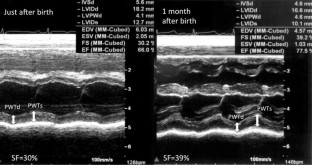

Fig. 1